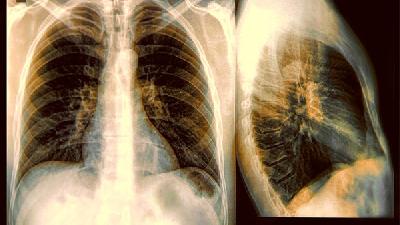

肺纖維化在如今的社會上發(fā)病率一直居高不下,萬幸的是我們的醫(yī)療水平也在不斷提高,只要我們能夠早日發(fā)現這個疾病并加以治療的話,想要康復并不難,今天將為大家講述中醫(yī)治療肺纖維化的方法,相信一定會對廣大的患者朋友有所幫助。

肺纖維化這種疾病嚴重的危害了患者的生活,這種疾病會造成很多的患者因為困難,出現很多的嚴重后果,所以發(fā)現疾病我們要積極的進行治療,爭取把疾病控制在最初的狀態(tài),另外在治療的過程中要選擇正規(guī)的醫(yī)院,最后祝廣大的患者朋友能夠早日的康復。